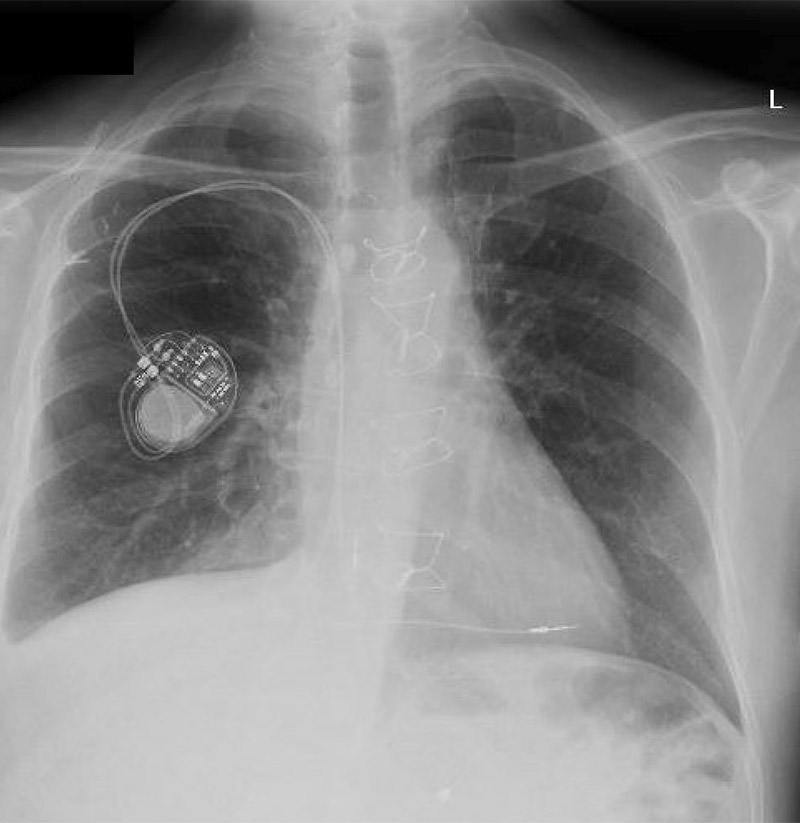

chest x-ray

Standard posterior-anterior (PA) chest x-ray is shown from a transplant recipient requiring permanent pacemaker implantation for sinus node dysfunction.